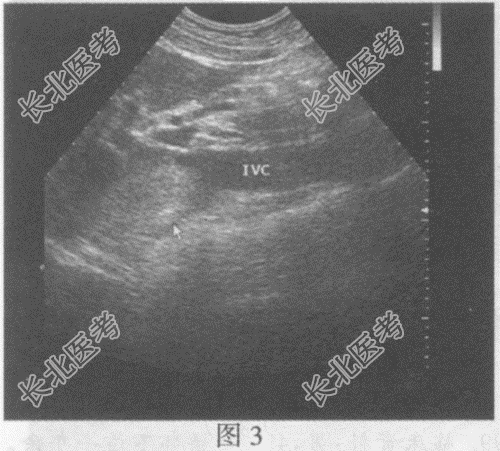

右肾静脉、下腔静脉肝后段管腔增宽,内可见中等回声(图2、图3), CDFI:该段内血流信号充盈缺损。